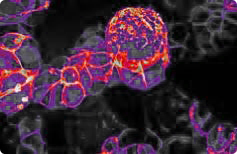

AI enhances healthcare outcomes by enabling faster, more accurate diagnoses, improving treatment planning, and assisting in patient monitoring. Machine learning models can detect diseases earlier, such as lung conditions in X-rays, classify body parts in medical imaging, and even analyze tissue samples to identify anomalies. AI-driven solutions also support predictive health analytics, allowing healthcare providers to anticipate and prevent potential complications, ultimately leading to better patient care and reduced hospitalizations.